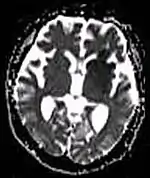

| Diffusion weighted (DWI) | Conventional | DWI | Measure of Brownian motion of water molecules.[78] | High signal within minutes of cerebral infarction (pictured).[79] |  |